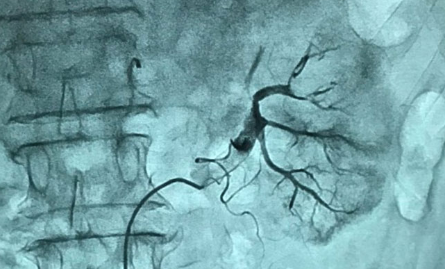

Các bác sĩ can thiệp cho người bệnh và hình ảnh mạch thận được thiết lập tuần hoàn sau khi lấy huyết khối. Ảnh: BVCC

Các bác sĩ đánh giá việc lấy huyết khối nhanh chóng có vai trò rất lớn trong việc bảo toàn chức năng cho thận. "Nếu để quá lâu, máu không được lưu thông, bệnh nhân có thể suy thận khiến bộ phận này mất hoàn toàn chức năng", ThS.BS Hoàng Minh Quang, Bệnh viện Việt Nam - Thụy Điển Uông Bí, cho biết.

Trước đây, người bệnh tắc mạch thận thường được điều trị nội khoa, mất nhiều thời gian nhưng hiệu quả không cao. Hiện nay, bác sĩ ứng dụng kỹ thuật cao dưới sự hỗ trợ của hệ thống máy chụp hình số hóa xóa nền DSA, giúp việc lấy huyết khối động mạch diễn ra nhanh chóng, huyết khối được lấy ra nhằm tái thiết lập lại hệ tuần hoàn cho thận.